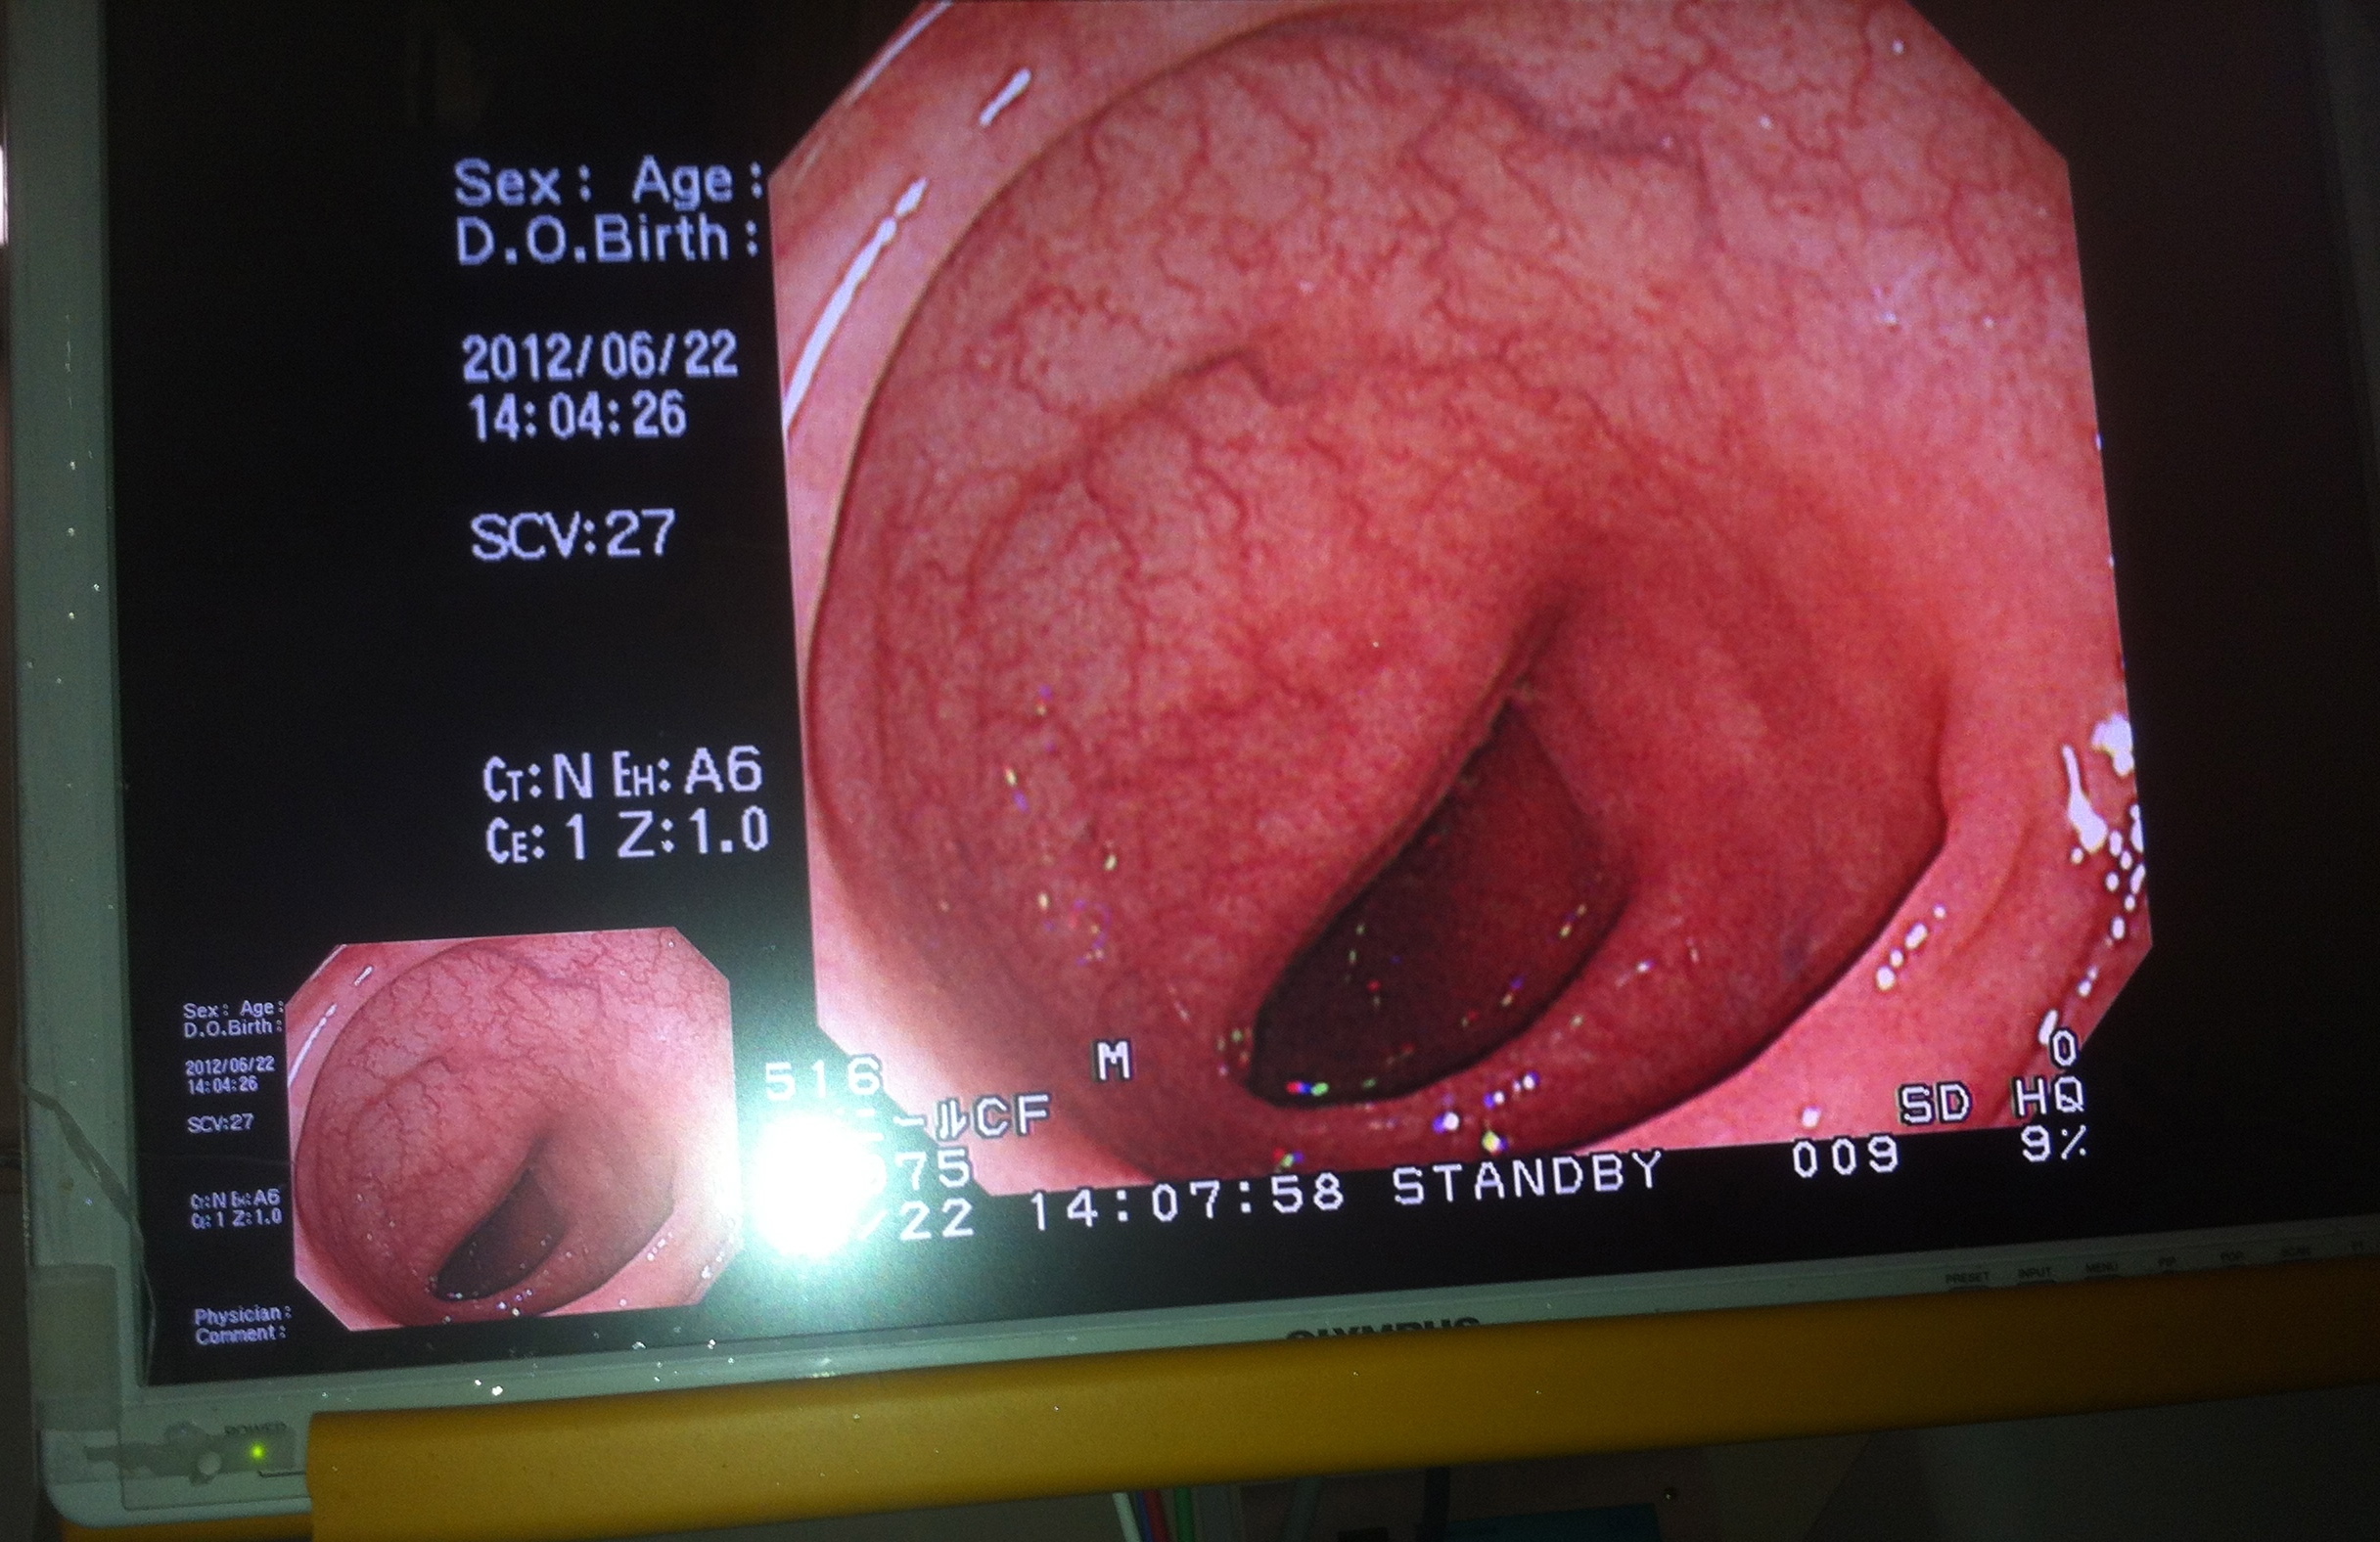

Essentially Kubota sensei inserts something into your private club which has a tool kit including a camera, nail clippers, electrical wire, a swiss army knife, spare tire etc attached to it. You have a wonderful business class seat with individual screen that allows you to watch the whole procedure.

Travel log along my colon. Getting ready to snip minor offenders. 48 shows electrical snare being wound around big boy polyp.

Kubota-sensei progresses up my colon occasionally halting to snip off some junior polyps until he comes to the big boy polyp. The technique is to inject what he calls ‘blue water’ in the tissue under the polyp and by so doing elevate and expose the the object of desire. An electrical snare is then wound around it and the offending growth is burnt off. The wound is then closed with clip things that are part of the tool kit.